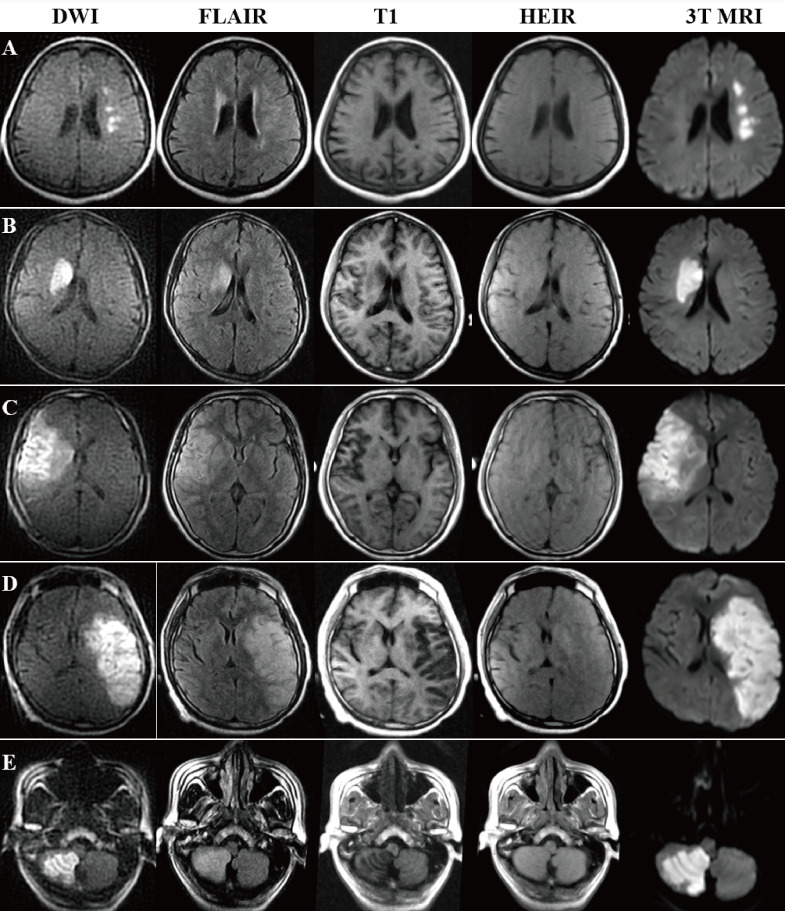

Methods: A novel HEIR sequence based on fluid-attenuated inversion recovery T1-weighted, with a scanning time of 1 min and 17 s, was developed using an ICH and AIS pig model on a 0.23-T MRI. Images of the pig model were obtained hourly for 24 hours in order to monitor value changes on T1/T2 and verify the differential diagnosis of AIS and ICH. Then, 30 patients with AIS and 30 patients with ICH with confirmed diagnoses by 3T-MRI/CT were included. Diagnostic criteria on a 0.23-T MRI for ICH was the hyperintensity signal on both the diffusion-weighted imaging (DWI) and HEIR sequence, while for AIS was the hyperintensity on DWI and isointensity on the HEIR sequence. Two blinded raters independently assessed the images obtained by the 0.23-T MRI for the presence of ICH/AIS.

Results: In the pig model, setting the inversion time to 800 ms enabled clear differentiation of ICH from brain parenchymal tissue and AIS. In real patients, a correct 0.23-T MRI diagnosis of either an AIS or ICH was made in all 60 patients within 24 hours of symptom onset (100% overall accuracy). No adverse events occurred.